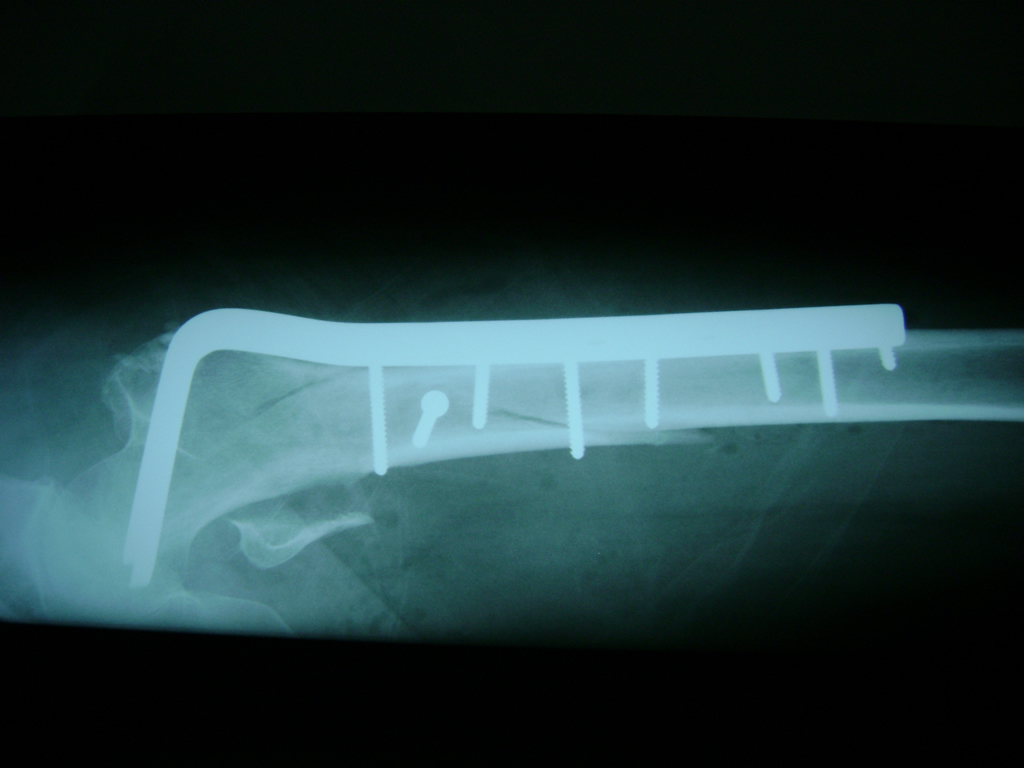

La cirugía de fractura de cadera se realiza para reparar una ruptura en la parte superior del hueso del muslo. Este hueso se denomina fémur.

Es parte de la articulación coxofemoral. Si una fractura de cadera no recibe tratamiento, es posible que deba permanecer en una silla o en la cama.

A menudo se recomienda la cirugía para reparar la fractura debido a dichos riesgos.